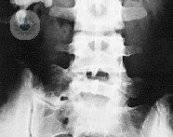

Litotricia extracorpórea por ondas de choque, el mejor tratamiento en litiasis renal infantil

Según investigaciones del Dr. Pérez-Castro, la litotricia extracorpórea por ondas de choque se ha constituido como el mejor tratamiento en litiasis renal infantil. Descubre en qué consiste el tratamiento.